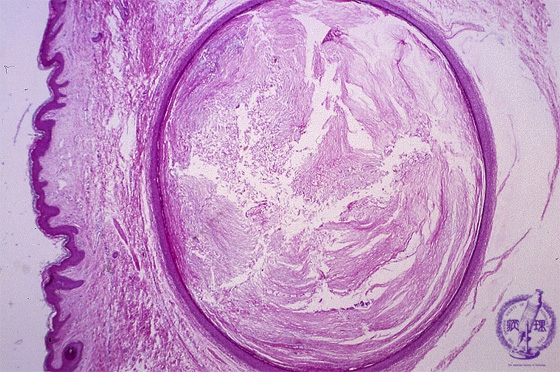

Microscopic findings: The cyst is filled with keratinizing materials. The wall does not contain skin appendages.